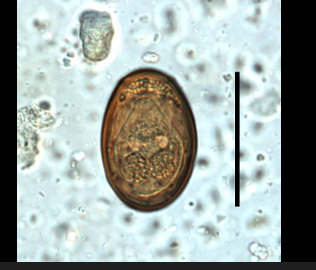

ERYTHOMA PANCREATICUM OVA W.M